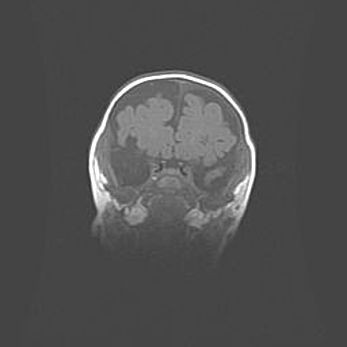

Сообщающаяся гидроцефалия. Кистозная энцефаломаляция головного мозга.

Возраст: 3 месяца 4 дня

Вес: 3100 г

Пол: женский

Окружность головы: 34 см

Срок гестации: 31 неделя

Кистозная энцефаломаляция головного мозга - одна из форм поражения головного мозга в детском возрасте. Характеризуется возникновением множественных и распространённых кист в коре, белом веществе и подкорковых образованиях головного мозга у плодов, новорождённых и детей раннего возраста. Развитие кистозной энцефаломаляции связано с внутриутробной асфиксией и гипотонией, родовой травмой, тромбозом синусов, пороками развития сосудов, инфекциями, сепсисом и другими причинами. Наиболее значимые инфекционные агенты: вирусы простого герпеса, цитомегалии, краснухи, токсоплазмы, энтеробактерии, золотистый стафилококк и другие.